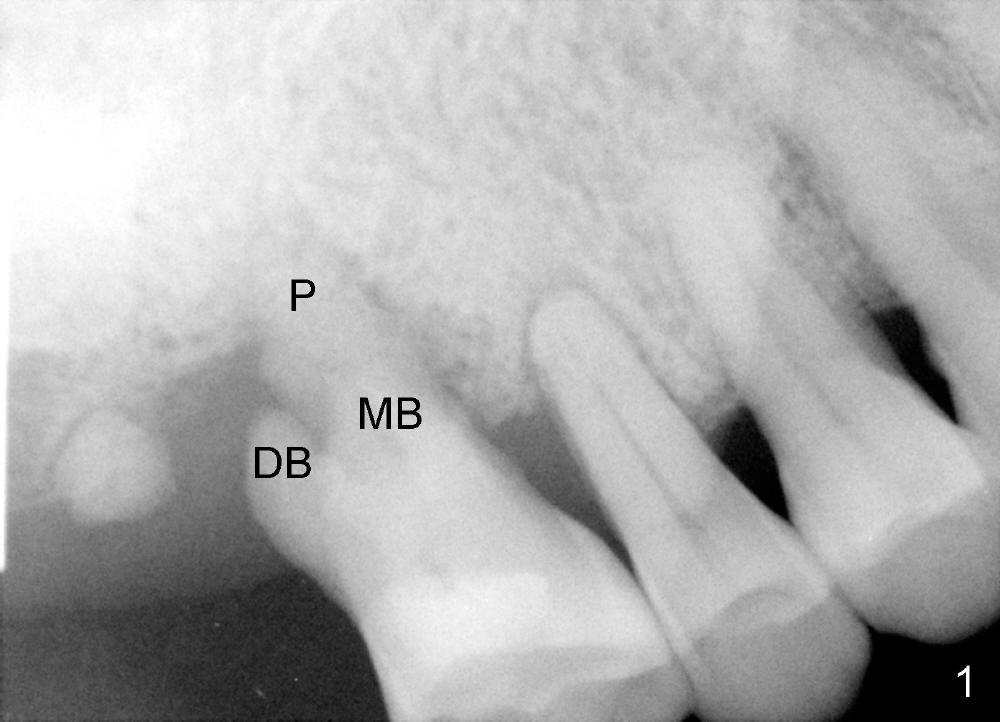

A 68-year-old lady presents to clinic with chief complaint of upper right pain. The tooth #3 has advanced periodontitis, compounded by occlusal trauma (Fig.1). There is severe bone loss, especially around the buccal roots, MB and DB. The latter are exposed (Fig.2,3).